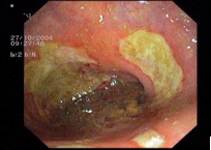

imagen2

Sarcoma de Kaposi a l'estómac - Tumor submucós esofàgic